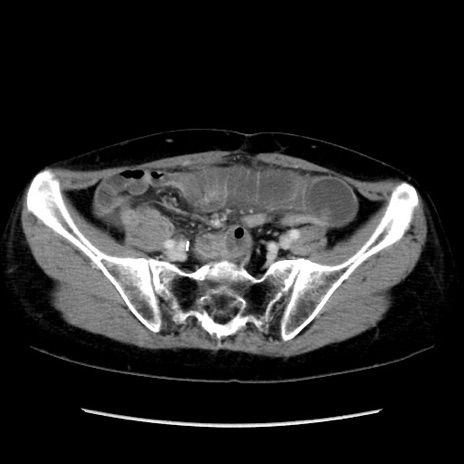

症例32(横断像)

【症例】40歳代 女性

【主訴】上腹部痛、嘔気・嘔吐

【現病歴】約9時間前頃から急に上腹部痛、嘔気、嘔吐が出現。改善しないため救急要請。

【既往歴】子宮頚癌(広汎子宮全摘術、放射線療法)、腸閉塞

【身体所見】腹部:平坦、軟、腸雑音亢進、上腹部を中心に腹部全体に圧痛あり。

【データ】WBC 8400、CRP 0.03